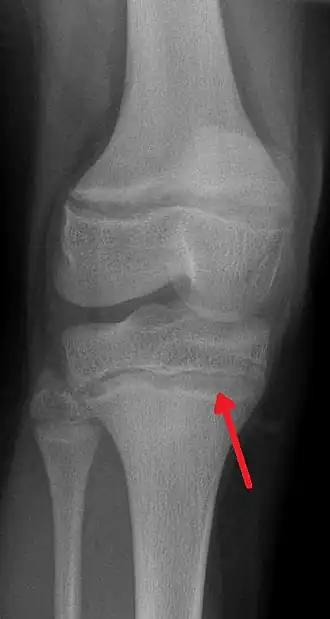

Raio X mostrando a característica linha de chumbo na metáfise da tíbia.